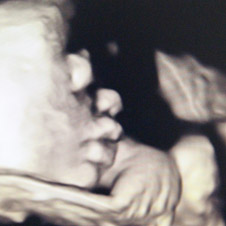

3 D / 4 D 超 音 波 診 断

3D/4D超音波検査とは

当院では最新型の 3D/4D の超音波診断装置を導入し、

妊娠中のお腹の中の赤ちゃんの立体動画を見ることが

出来るようになりました。

3D による鮮明な赤ちゃんの立体画像とその 3D 画像が

リアルタイムで動く 4D 機能により、赤ちゃんが笑ったり、

あくびをしたり、指をしゃぶったり、手足を動かしている

様子を見る事が出来ます。

それによってお腹の赤ちゃんの成長、親子の絆、

大切さや愛おしさをより実感されることと思います。

画像は当院で撮影した妊娠11週から16週のお腹の赤ちゃんです。

大切な命の誕生に出会えた瞬間です。